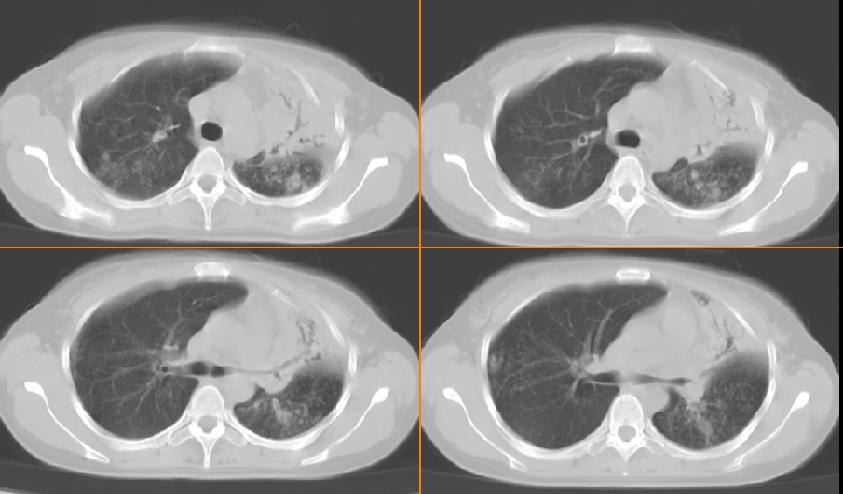

女,33岁,咳嗽5月。

左肺上叶前段致密,内见空气支气管征,相应部位胸膜增厚粘连,双肺上其他肺叶不同程度斑片状播散病灶,结合咳嗽5月的病史,考虑:双肺上叶继发性肺结核。

双上肺、左下肺背段肺结核,左上肺膨胀不全.

支持双上肺结核(左肺上叶干酪性肺炎)。

左肺上叶前段致密,内见空气支气管征,相应部位胸膜增厚粘连,双肺上其他肺叶不同程度斑片状播散病灶,结合咳嗽5月的病史,考虑:双肺上叶继发性肺结核伴左肺上叶肺含气不良。